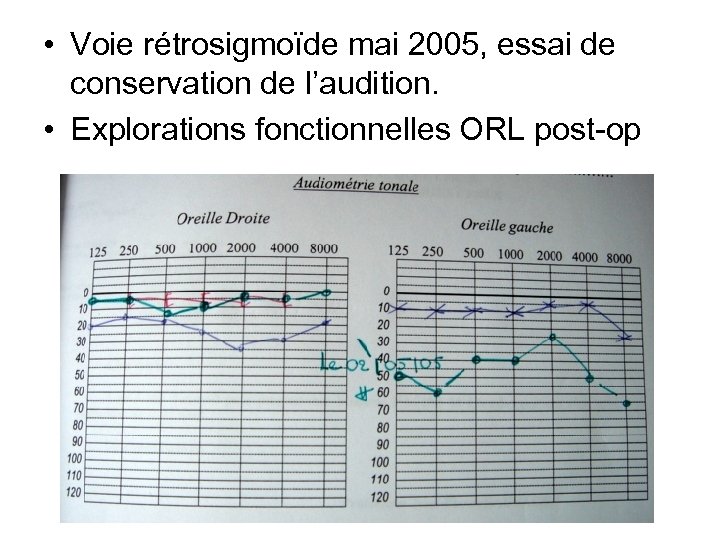

• Voie rétrosigmoïde mai 2005, essai de conservation de l’audition. • Explorations fonctionnelles ORL post-op

• Voie rétrosigmoïde mai 2005, essai de conservation de l’audition. • Explorations fonctionnelles ORL post-op